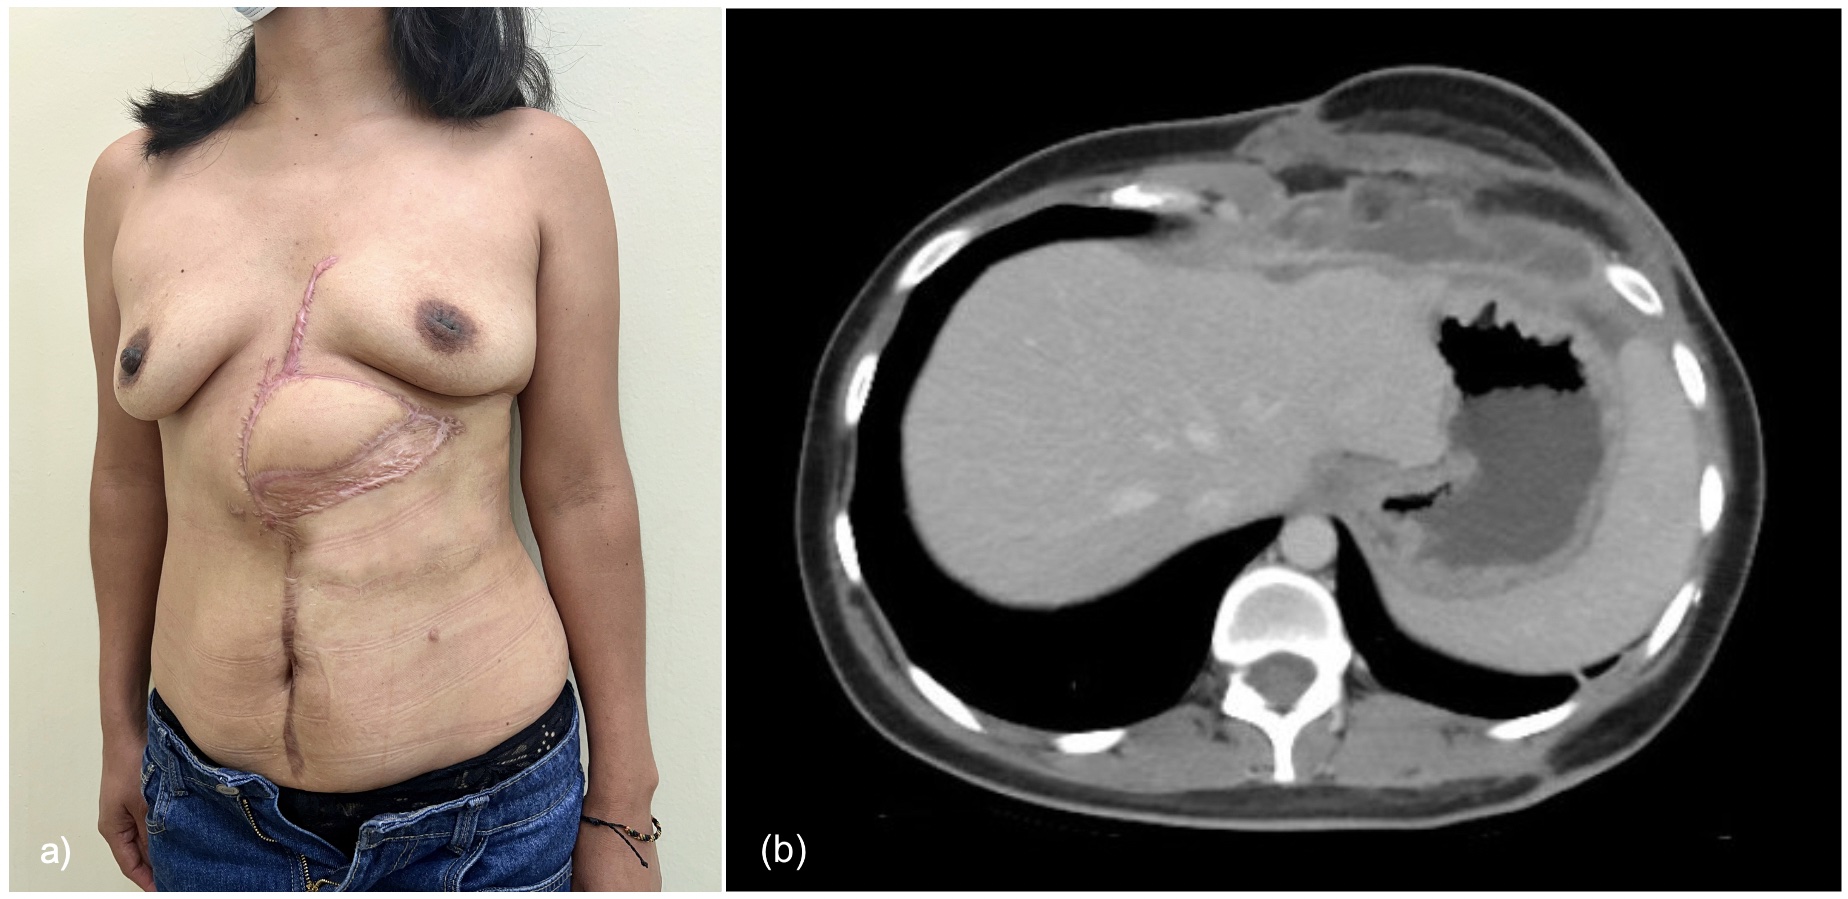

Salvage reconstruction with a vascularized latissimus dorsi (LD) myocutaneous free flap was performed using the left internal mammary vessels as recipient (Figure 3). Total hospitalization length was 18 days. Eight weeks after surgery, the patient exhibited a well-perfused flap with all the surgical wounds adequately healed. Computed tomography scan showed satisfactory restoration of the abdominal wall integrity (Figure 4).

Figure 4. Six months after surgery, patient showing a well-perfused flap, with a totally incorporated skin graft, and all the surgical wounds adequately healed (A). Computed tomography scan showed satisfactory restoration of the abdominal wall integrity (B).